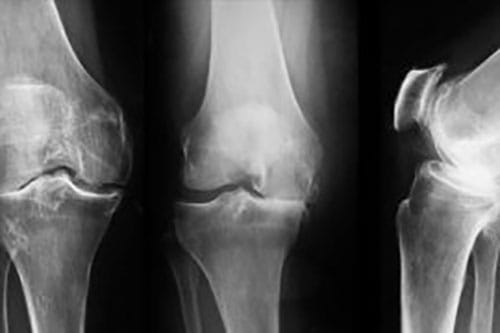

Cu siguranta ati ghicit! Scaderea cantitatii de lichid sinovial, cel ce tine articulatia in tensiune si citochinele pro-inflamatorii duc la frecarea anormala a capetelor oaselor si la distructia suprafetelor articulare. Astfel apare modificarea radiologica a articulatiei si, implicit, durerea.

De fapt, ce anume din suprafata articulara se distruge?

- cartilajul hialin

Sa va explic de ce varianta 1 de raspuns e cea corecta: bursele nu sunt cele de marfuri ci niste structuri care, din fericire, nu au nici o treaba cu artroza. Cartilajul fibros e cel pe care il rupem la schi sau la fotbal, adica meniscurile, iar capsula articulara e un raspuns prea general – ramanand in joc doar cartilajul hialin adica cel ce permite, in mod normal alunecarea fina a capetelor osoase.